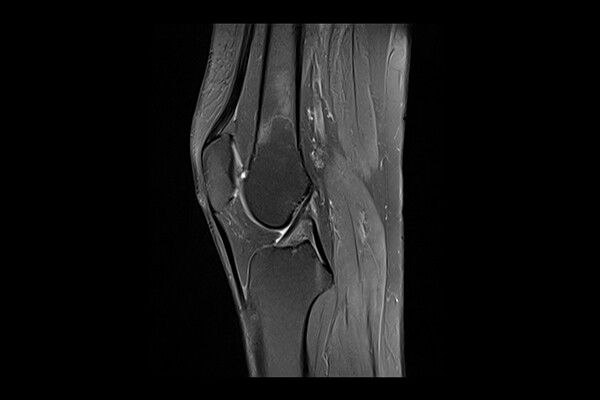

• To heal meniscus injuries, researchers go to the heart of a cell

Using an enzyme inhibitor in meniscus cells, a Penn team is able to soften the cells’ nucleus and promote access to previously impassible tissue.